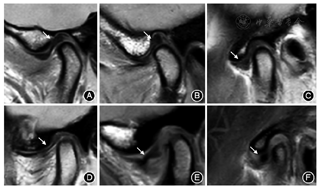

①简单评估,闭口位为倒置"S"型,张口位"领结"型[8,9,10];②关节盘厚度评估(各带最大厚度),前带2 mm,中间带1.1 mm,后带2.8 mm;③常见关节盘形态学包括双凹型、后带增厚型、前带增厚型、拉伸型、折叠型及类圆形(图1)[10,11]。